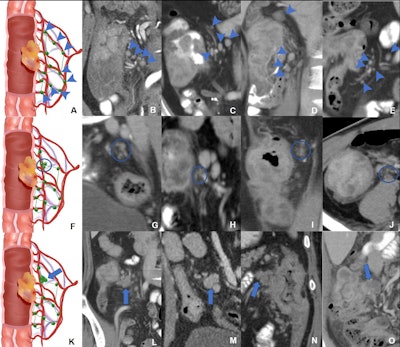

Schematic diagrams and representative images of different distribution patterns of region lymph nodes detected at CT. (A) Vascular distribution pattern: All regional lymph nodes detected at CT have regular borders and are distributed along the vessels (arrowheads). (B-E) Coronal CT images in a (B) 34-year-old woman, (C) 51-year-old man, (D) 37-year-old man, and (E) 40-year-old man with microsatellite instability-high (MSI-H) colon cancer show multiple clear lymph nodes distributed along the supplying arteries or draining veins (arrowheads). (F) Jammed cluster pattern: At least three lymph nodes with blurred margins and clustered (circle). (G-I) Coronal CT images in a (G) 29-year-old man, (H) 35-year-old man, and (I) 67-year-old man and (J) axial CT image in a 43-year-old man with MSI-H colon cancer show several lymph nodes with blurred margins and clustered (circle). Movies 1-4 provide more details. (K) Fused pattern: Several poorly defined lymph nodes clustered and fused together (arrow). (L-O) Coronal CT images in a (L) 63-year-old woman, (M) 59-year-old man, (N) 49-year-old woman, and (O) 73-year-old man with MSI-H colon cancers show several lymph nodes fused (arrow). Image courtesy of Radiology.